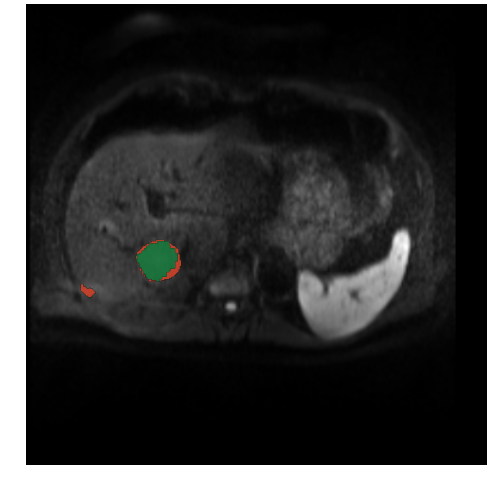

3.3.3 Qualitative and Quantitative Results

As seen in figure 8, the CFCN was able to segment the liver lesion correctly. In both cases the CFCN undersegments the lesion leading to a Dice score of 85% in both cases. The quantitative segmentation results are shown in table 1. The Cascaded U-Net was able to reach a dice score for liver in MR-DWI of 87%. For lesion we found a mean dice score of 69.7%.

Refer to caption

Figure 8: Automatic lesion segmentation with cascaded fully convolutional neural networks (CFCN) in DW-MRI. The raw DW-MRI slices (left), were automatically segmented with our proposed method. Green depicts correctly segmented lesion pixels. Red shows false positive and false negative, i.e. all wrong predictions, of the lesions. In both cases the proposed CFCN achieves an dice score for lesions of 85%.